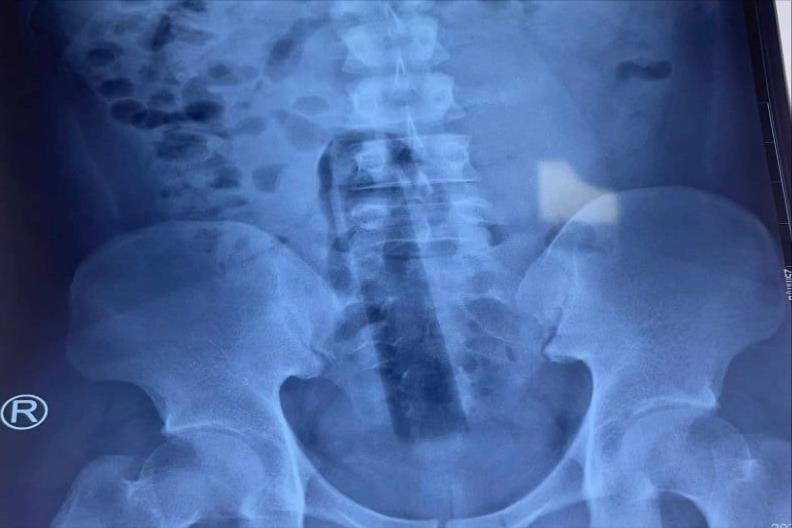

Dị vật cán cây lau nhà 15cm mắc kẹt trong hậu môn của nam thanh niên

Trường hợp người bệnh P.T.P (23 tuổi) nhập viện trong tình trạng đau dữ dội vùng hậu môn, bí trung đại tiện, bụng chướng đau do cán cây lau nhà 15cm mắc kẹt trong hậu môn.